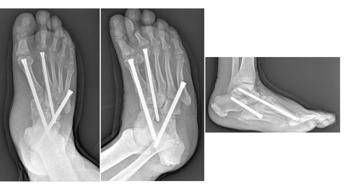

“Sono interventi che mirano a correggere deformità estremamente complesse del piede e della caviglia – illustra Perisano – e che prevedono una serie di procedure chirurgiche (nell’ambito dello stesso intervento), quali osteotomie correttive e successive osteosintesi. Questo consente la ricostruzione di un asse del piede e della caviglia, per permettere al paziente di tornare a camminare (in genere entro un paio di mesi dall’intervento). I pazienti affetti da questa condizione infatti non riescono più a deambulare perché queste deformità comportano alterazioni dell’appoggio, che sottopongono alcune zone del piede, normalmente non deputate a sostenere il carico, ad una pressione eccessiva che a sua volta può portare ad ulcerazioni; queste, nei pazienti diabetici (che spesso sono anche vasculopatici), possono causare infezioni gravi e profonde, che a loro volta comportano un elevato rischio di amputazione”.